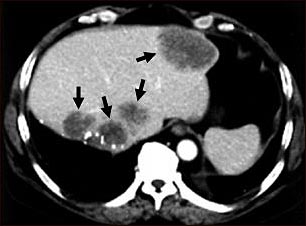

TC de metástasis hepática

TC de la parte superior del abdomen de un paciente con carcinoma del intestino grueso que muestra metástasis múltiple hacia el hígado. Observar las áreas oscuras en el hígado (lado izquierdo y al centro de la imagen).